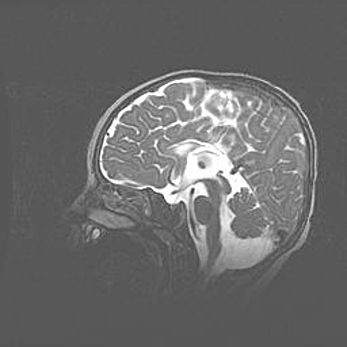

Аномалия Денди-Уокера. Признаки гипоплазии мозолистого тела.

Возраст: 5 месяцев 3 дня

Вес: 5550 г

Пол: мужской

Окружность головы: 39 см

Срок гестации: 40 недель

Аномалия Денди-Уокера – это порок развития головного мозга, для которого характерна триада симптомов: гипотрофия или аплазия червя мозжечка и/или полушарий мозжечка, расширение четвёртого желудочка с формированием ликворной кисты задней черепной ямки, гипертензионная гидроцефалия различной степени.

Гипоплазия мозолистого тела относится к дефектам внутриутробного этапа развития мозговой ткани, возникающим в процессе закладки структур головного мозга, что происходит на начальных этапах развития эмбриона.